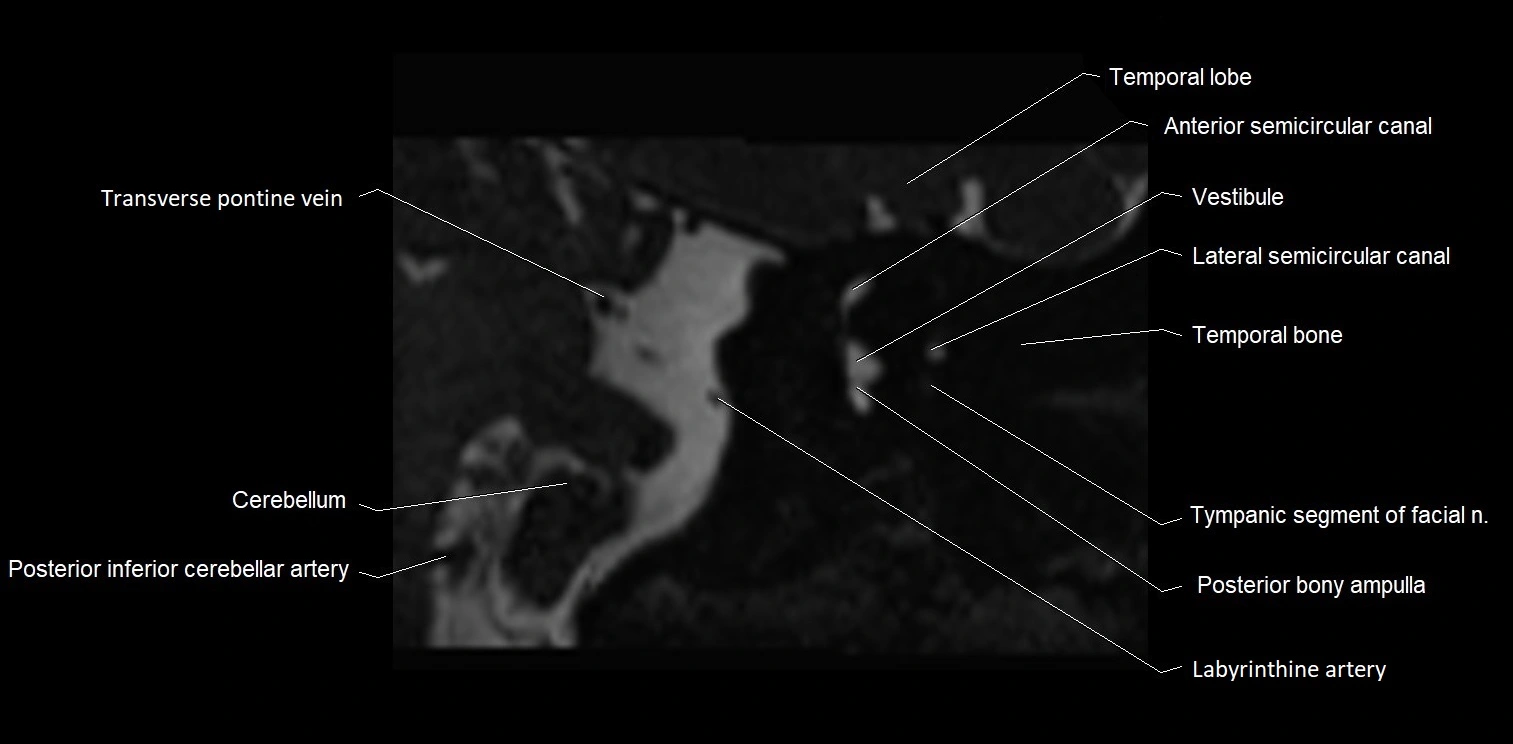

MRI Appearance

• The abducens nerve is a small, thin, linear structure

• Best visualized on high-resolution T2-weighted 3D MRI sequences (e.g., FIESTA or CISS)

• Seen as a hypointense (dark) line running from the brainstem at the pontomedullary junction, traversing the prepontine cistern, and entering Dorello’s canal under the petrosphenoidal ligament, then into the cavernous sinus, and finally the orbit

• May be challenging to visualize in standard MRI due to its small size

• Pathology may be inferred by absence, displacement, or enhancement of the nerve